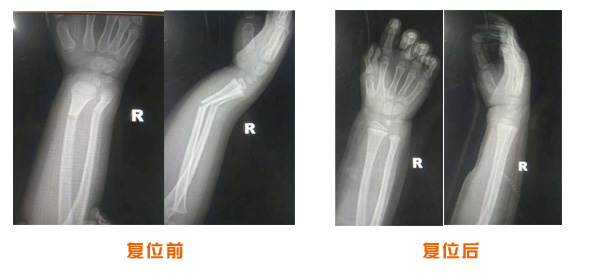

肥城市安駕莊梁氏骨科醫(yī)院是一所以梁氏手法正骨配合膏藥為特色的現(xiàn)代化專(zhuān)科醫(yī)院。

梁氏骨科術(shù)始創(chuàng)于清雍正年間,歷經(jīng)八代,至今已有三百年歷史。據(jù)1929年泰安縣志載“梁瑞圖先生,字增生,號(hào)蓮峰,安駕莊人,精岐黃并發(fā)明接骨,凡跌打車(chē)凡跌打車(chē)軋皮不破而碎骨者......【詳細(xì)】 |